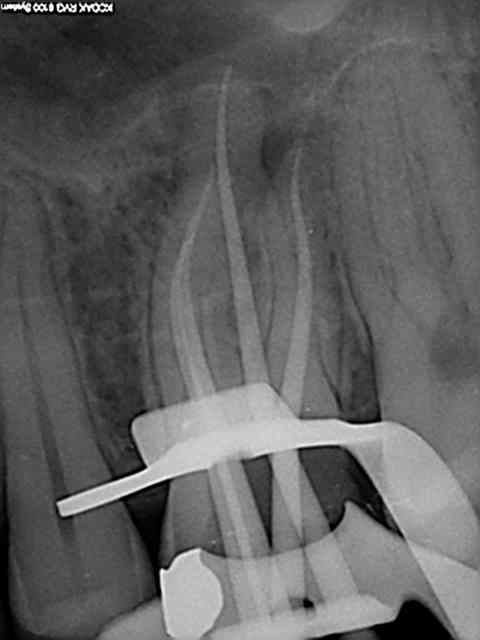

Radio cone en place avant obturation, j'ai rarement un problème avec le mv2 avec lequel soit je n'arrive pas à l'apex soit je bute sur la paroi du mv1 si ceux ci sont en y. Jamais de cathétérisme manuel seulement une localisation d'apex au S1 protaper sur endomaster, repère visuel sur les graduations puis r25. récapitulation en plusieurs fois si les instruments forcent toutefois. Je vais essayer la localisation au gold pour voir si ca dit la meme chose que l'endo master. Ci dessous l'endo molaire du jour c'est tout frais (en général je poste les endos de la journée) ici en l'occurrence patient vu pour la premiere fois, status radio + endo 45 mn.

Ca c'est cones en place))))), la cavité distale ne m'a pas dérangée dans ce cas (digue bien plaquée en distal et étanche) , sinon oui je fais une reconstitution pré endo si il y a des fuites.

Jamais de limes en place (j'en ai pas) localisation au s1 sur endo master uniquement puis éventuellement avec un mtwo 25 à la fin pour être sur d'être à l'apex en 25 -06 (une formalité).